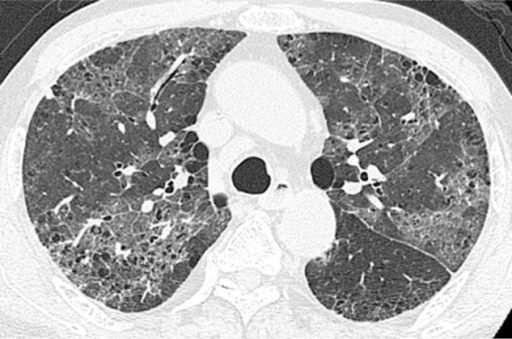

Puzzle 10

What's the Diagnosis?